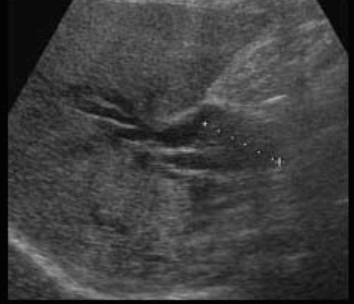

US finding

- 담관 내 무에코의 낭종

- 경계가 분명한 후방음향 증강

- 지방식 검사 후 수축소견이 없다.